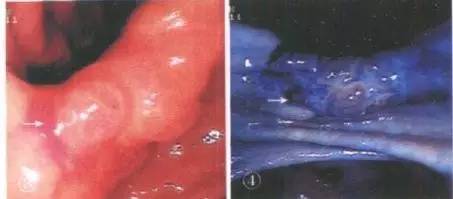

Barett食管碘染后,病变区域不染色,正常区域呈棕褐色

胃角部美蓝染色,癌变区域染色深蓝